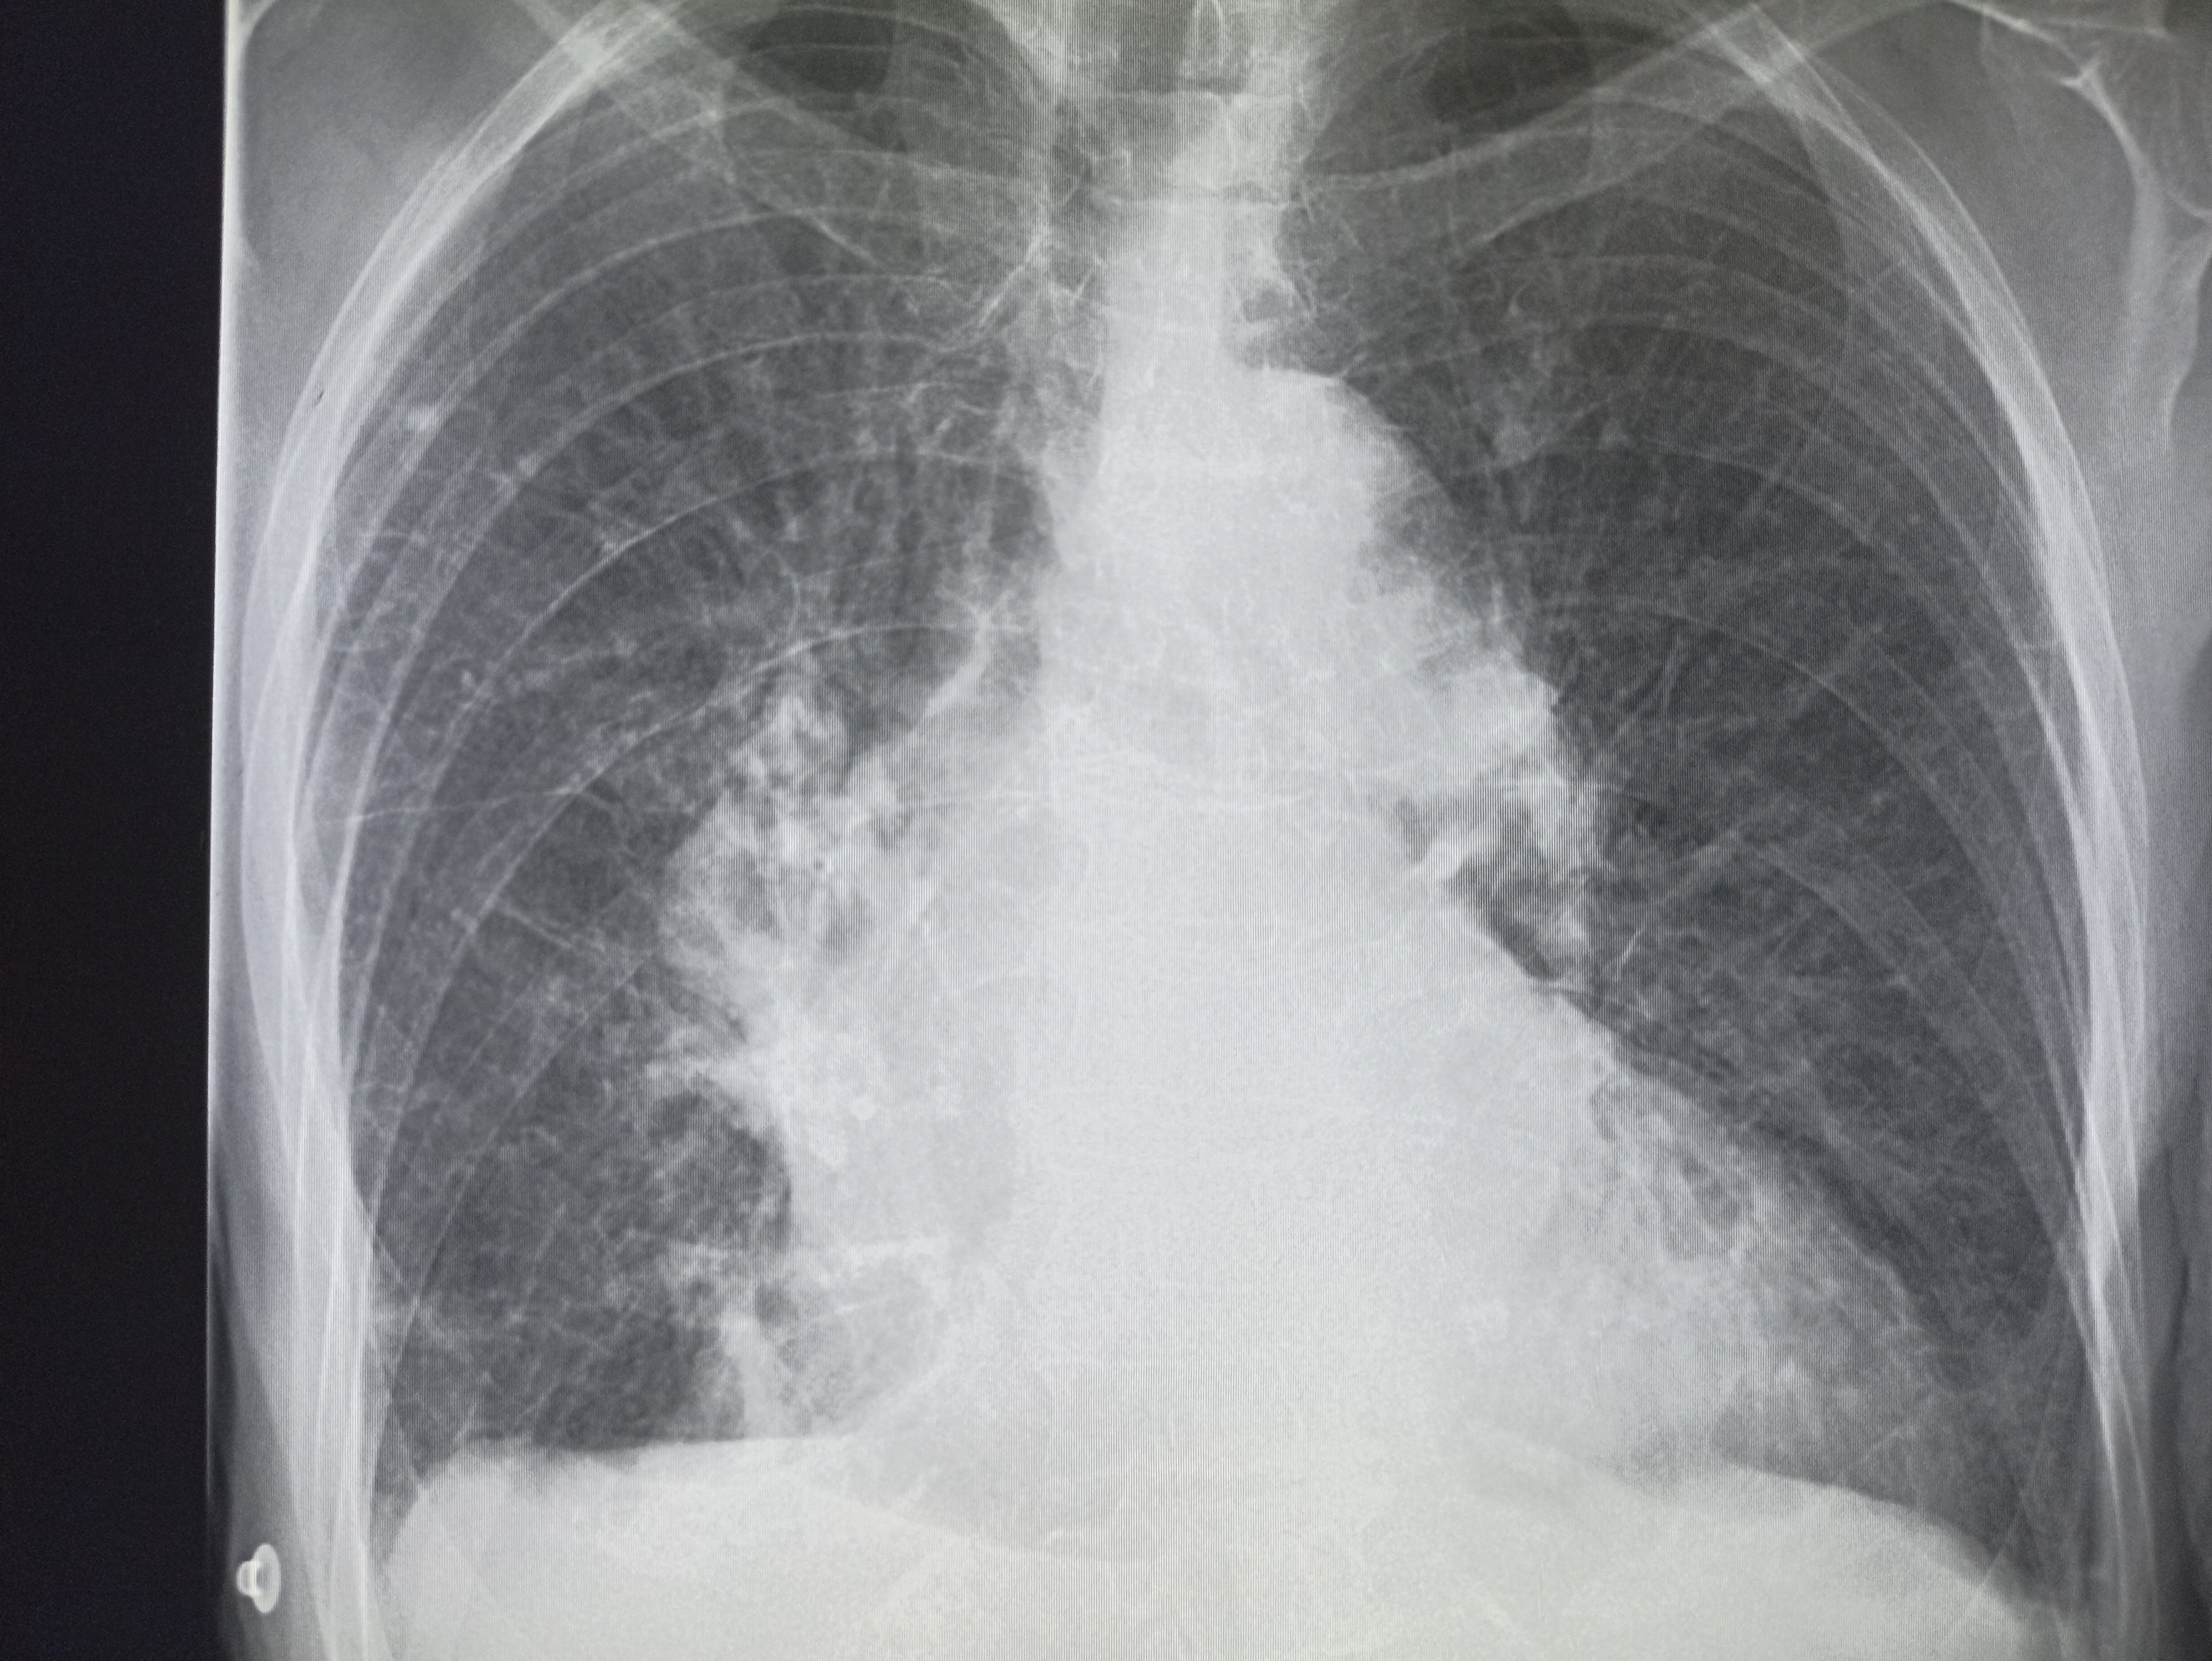

Здравствуй двачик, пишет вам простой рентгенолог из мухосранской поликлиники, сегодня я буду флексить зарплатой за ноябрь! Аж ПЯТЬДЕСЯТ ТРИ ТЫЩИ ПЕРЕВЕДУТ! С пруфом! А чего достигли вы? Ну и в доктора тож поиграем! Я буду вам картинки показывать, а вы пиздецомы находить! Найдите пиздецому на фтчк! Отчет еще по фог считать квартальный и годовой сегодня :-(